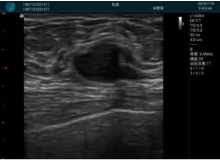

甲狀腺囊性結(jié)節(jié),囊壁鈣化,透聲好

甲狀腺囊性占位